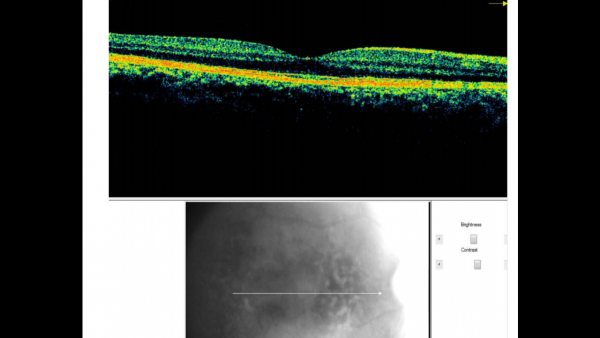

Fundus photos show multiple, yellow, round accumulations sub-RPE. Fundus autofluorescence often demonstrates more numerous hyperautofluorescent drusen than seen ophthalmoscopically. The drusen can demonstrate central hypo-autofluorescence and a rim of hyper-autofluorescence.[6][12] Fluorescein angiography reveals a greater number of small drusen than seen clinically during the early arterio-venous phase. These are spread diffusely throughout the macula, with a classic “stars in the sky” appearance.[6][7] Optical coherence tomography depicts RPE elevations due to drusen beneath the RPE with the most common appearance being a “saw-tooth” appearance as shown in the image below.[6][8]